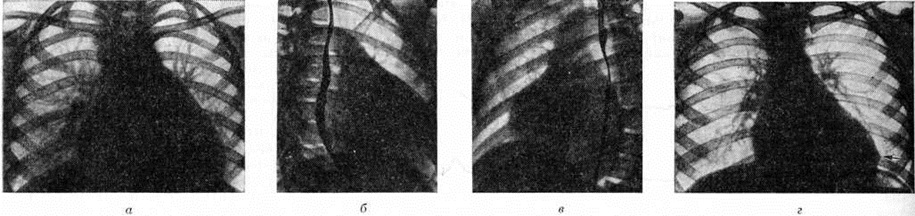

Информация об Ordo Deus Перейти в оглавление сайта

Рис. 10.

Рентгенограммы грудной клетки при активном эндомиокардите (вальвулит митрального клапана, адгезивный плевроперикардит, недостаточность кровообращения II А стадии): а — прямая проекция (сердце митральной конфигурации, увеличено в размерах); б — правая косая проекция (левое предсердие увеличено, пищевод отклонён по дуге большого радиуса); в — левая косая проекция (увеличение обоих желудочков, пищевод заполнен контрастным веществом); грамм — прямая проекция (после лечения) — нормализация размеров и конфигурации сердца; деформация нижне-левого контура сердца вследствие наличия плевроперикардиальной спайки (указана стрелкой).